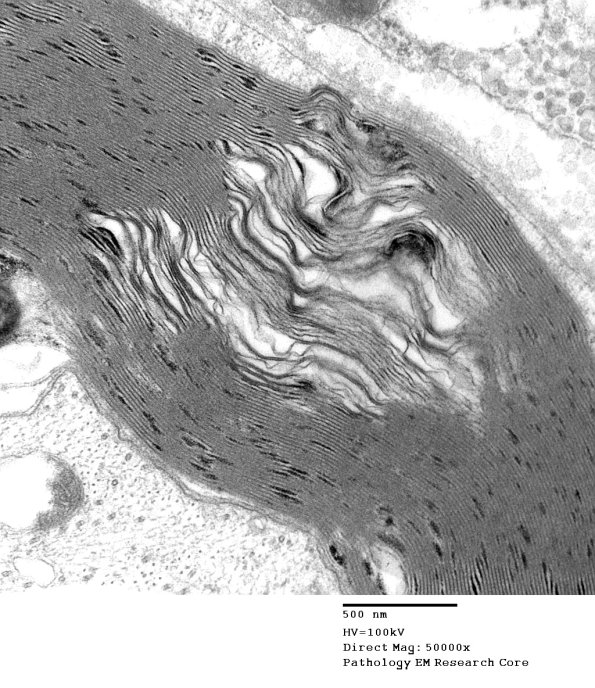

Washington University Experience | PERIPHERAL NEUROPATHY | 0 PNS ARTIFACTS | 7B2 Artifact, separation myelin, Amiodarone _006a - Copy

Small splits in the myelin sheath itself are common alterations thought to reflect problems with dehydration of the specimen during processing. (electron micrograph)